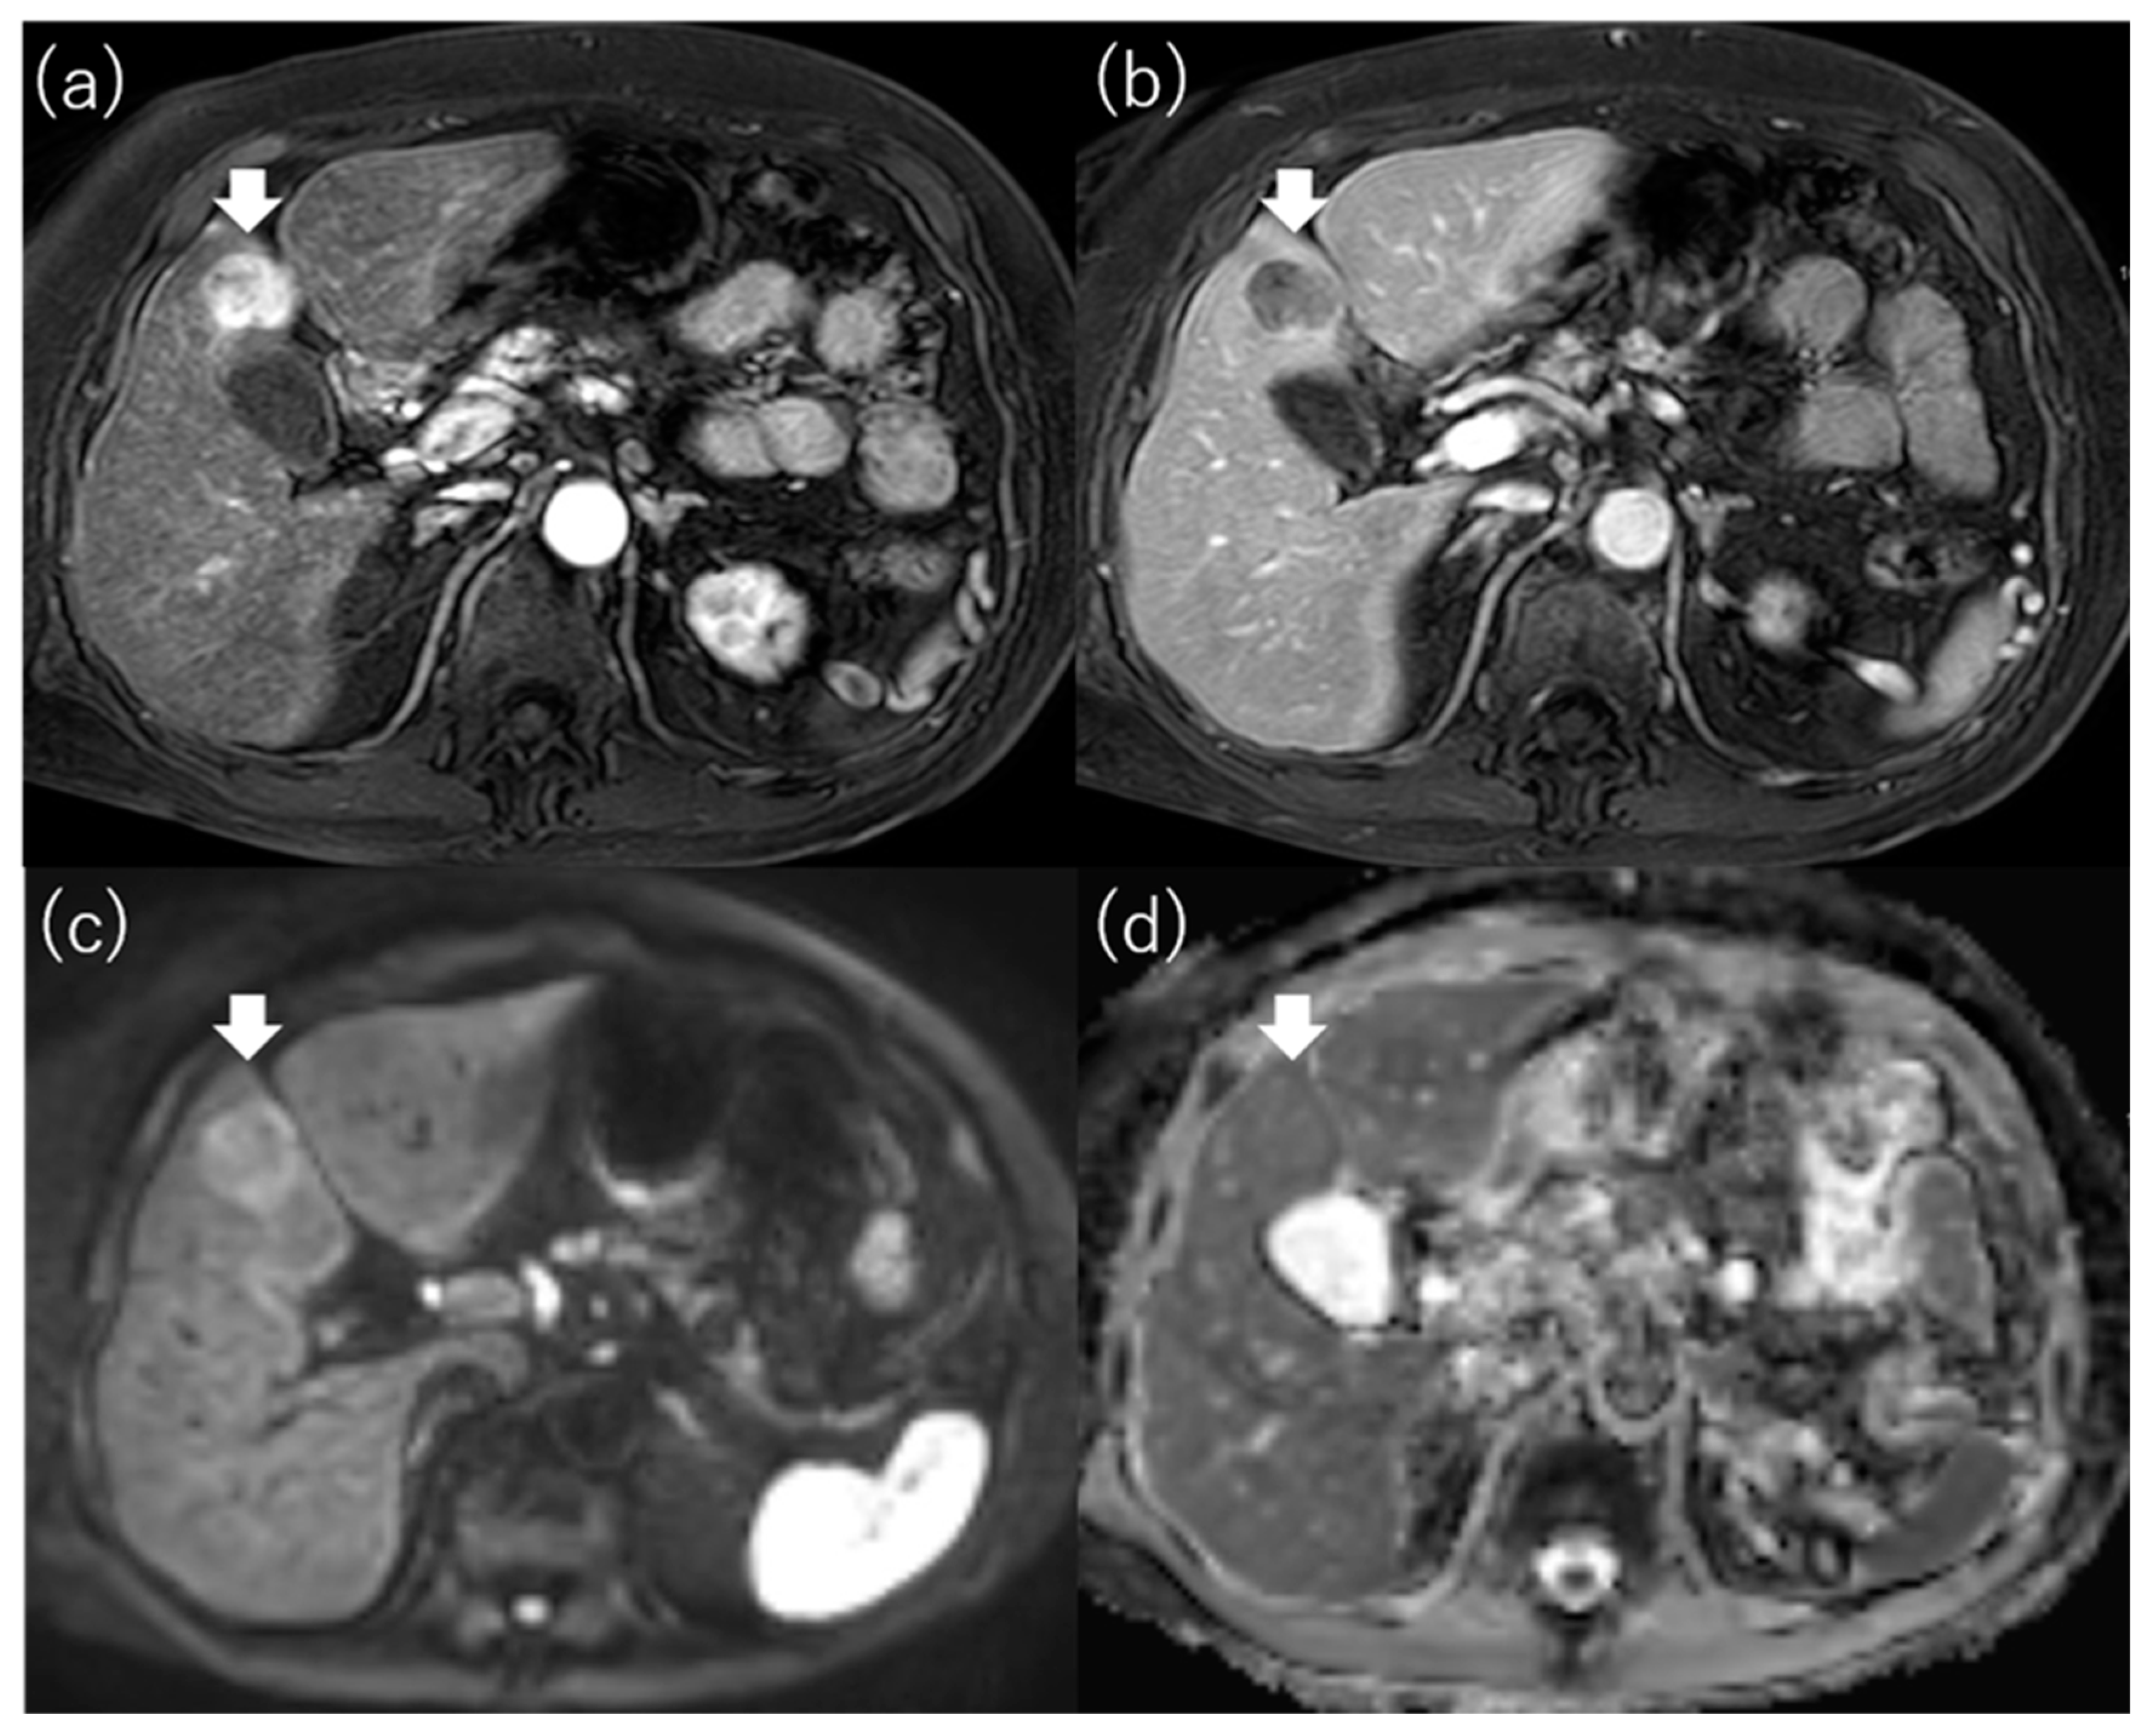

4.3. Diffusion-Weighted Imaging

- Mori, Y.; Tamai, H.; Shingaki, N.; Moribata, K.; Deguchi, H.; Ueda, K.; Inoue, I.; Maekita, T.; Iguchi, M.; Kato, J.; et al. Signal intensity of small hepatocellular carcinoma on apparent diffusion coefficient mapping and outcome after radiofrequency ablation. Hepatol. Res. Off. J. Jpn. Soc. Hepatol. 2015, 45, 75–87. [Google Scholar] [CrossRef]

- Mori, Y.; Tamai, H.; Shingaki, N.; Hayami, S.; Ueno, M.; Maeda, Y.; Moribata, K.; Deguchi, H.; Niwa, T.; Inoue, I.; et al. Hypointense hepatocellular carcinomas on apparent diffusion coefficient mapping: Pathological features and metastatic recurrence after hepatectomy. Hepatol. Res. Off. J. Jpn. Soc. Hepatol. 2016, 46, 634–641. [Google Scholar] [CrossRef]

| Mori et al. [68] | 136 | ≤3 tumors and ≤3 cm | RFA | Outcome (recurrence, OS) | Hypointensity on the ADC map was one of the independent factors for recurrence (HR, 2.651; 95% CI, 1.530–4.593; p = 0.001), local recurrence (HR, 5.602; 95% CI, 1.526–20.568; p = 0.009), critical recurrence (HR, 2.555; 95% CI, 1.171–5.571; p = 0.018), and survival (HR, 2.945; 95% CI, 1.124–7.721; p = 0.028). |

| Mori et al. [69] | 52 | Solitary and ≤5 cm | LR | Outcome (recurrence) | Hypointensity on the ADC map was one of the independent factors for metastatic recurrence (HR, 12.279; 95% CI, 1.486–101.48; p = 0.020). |